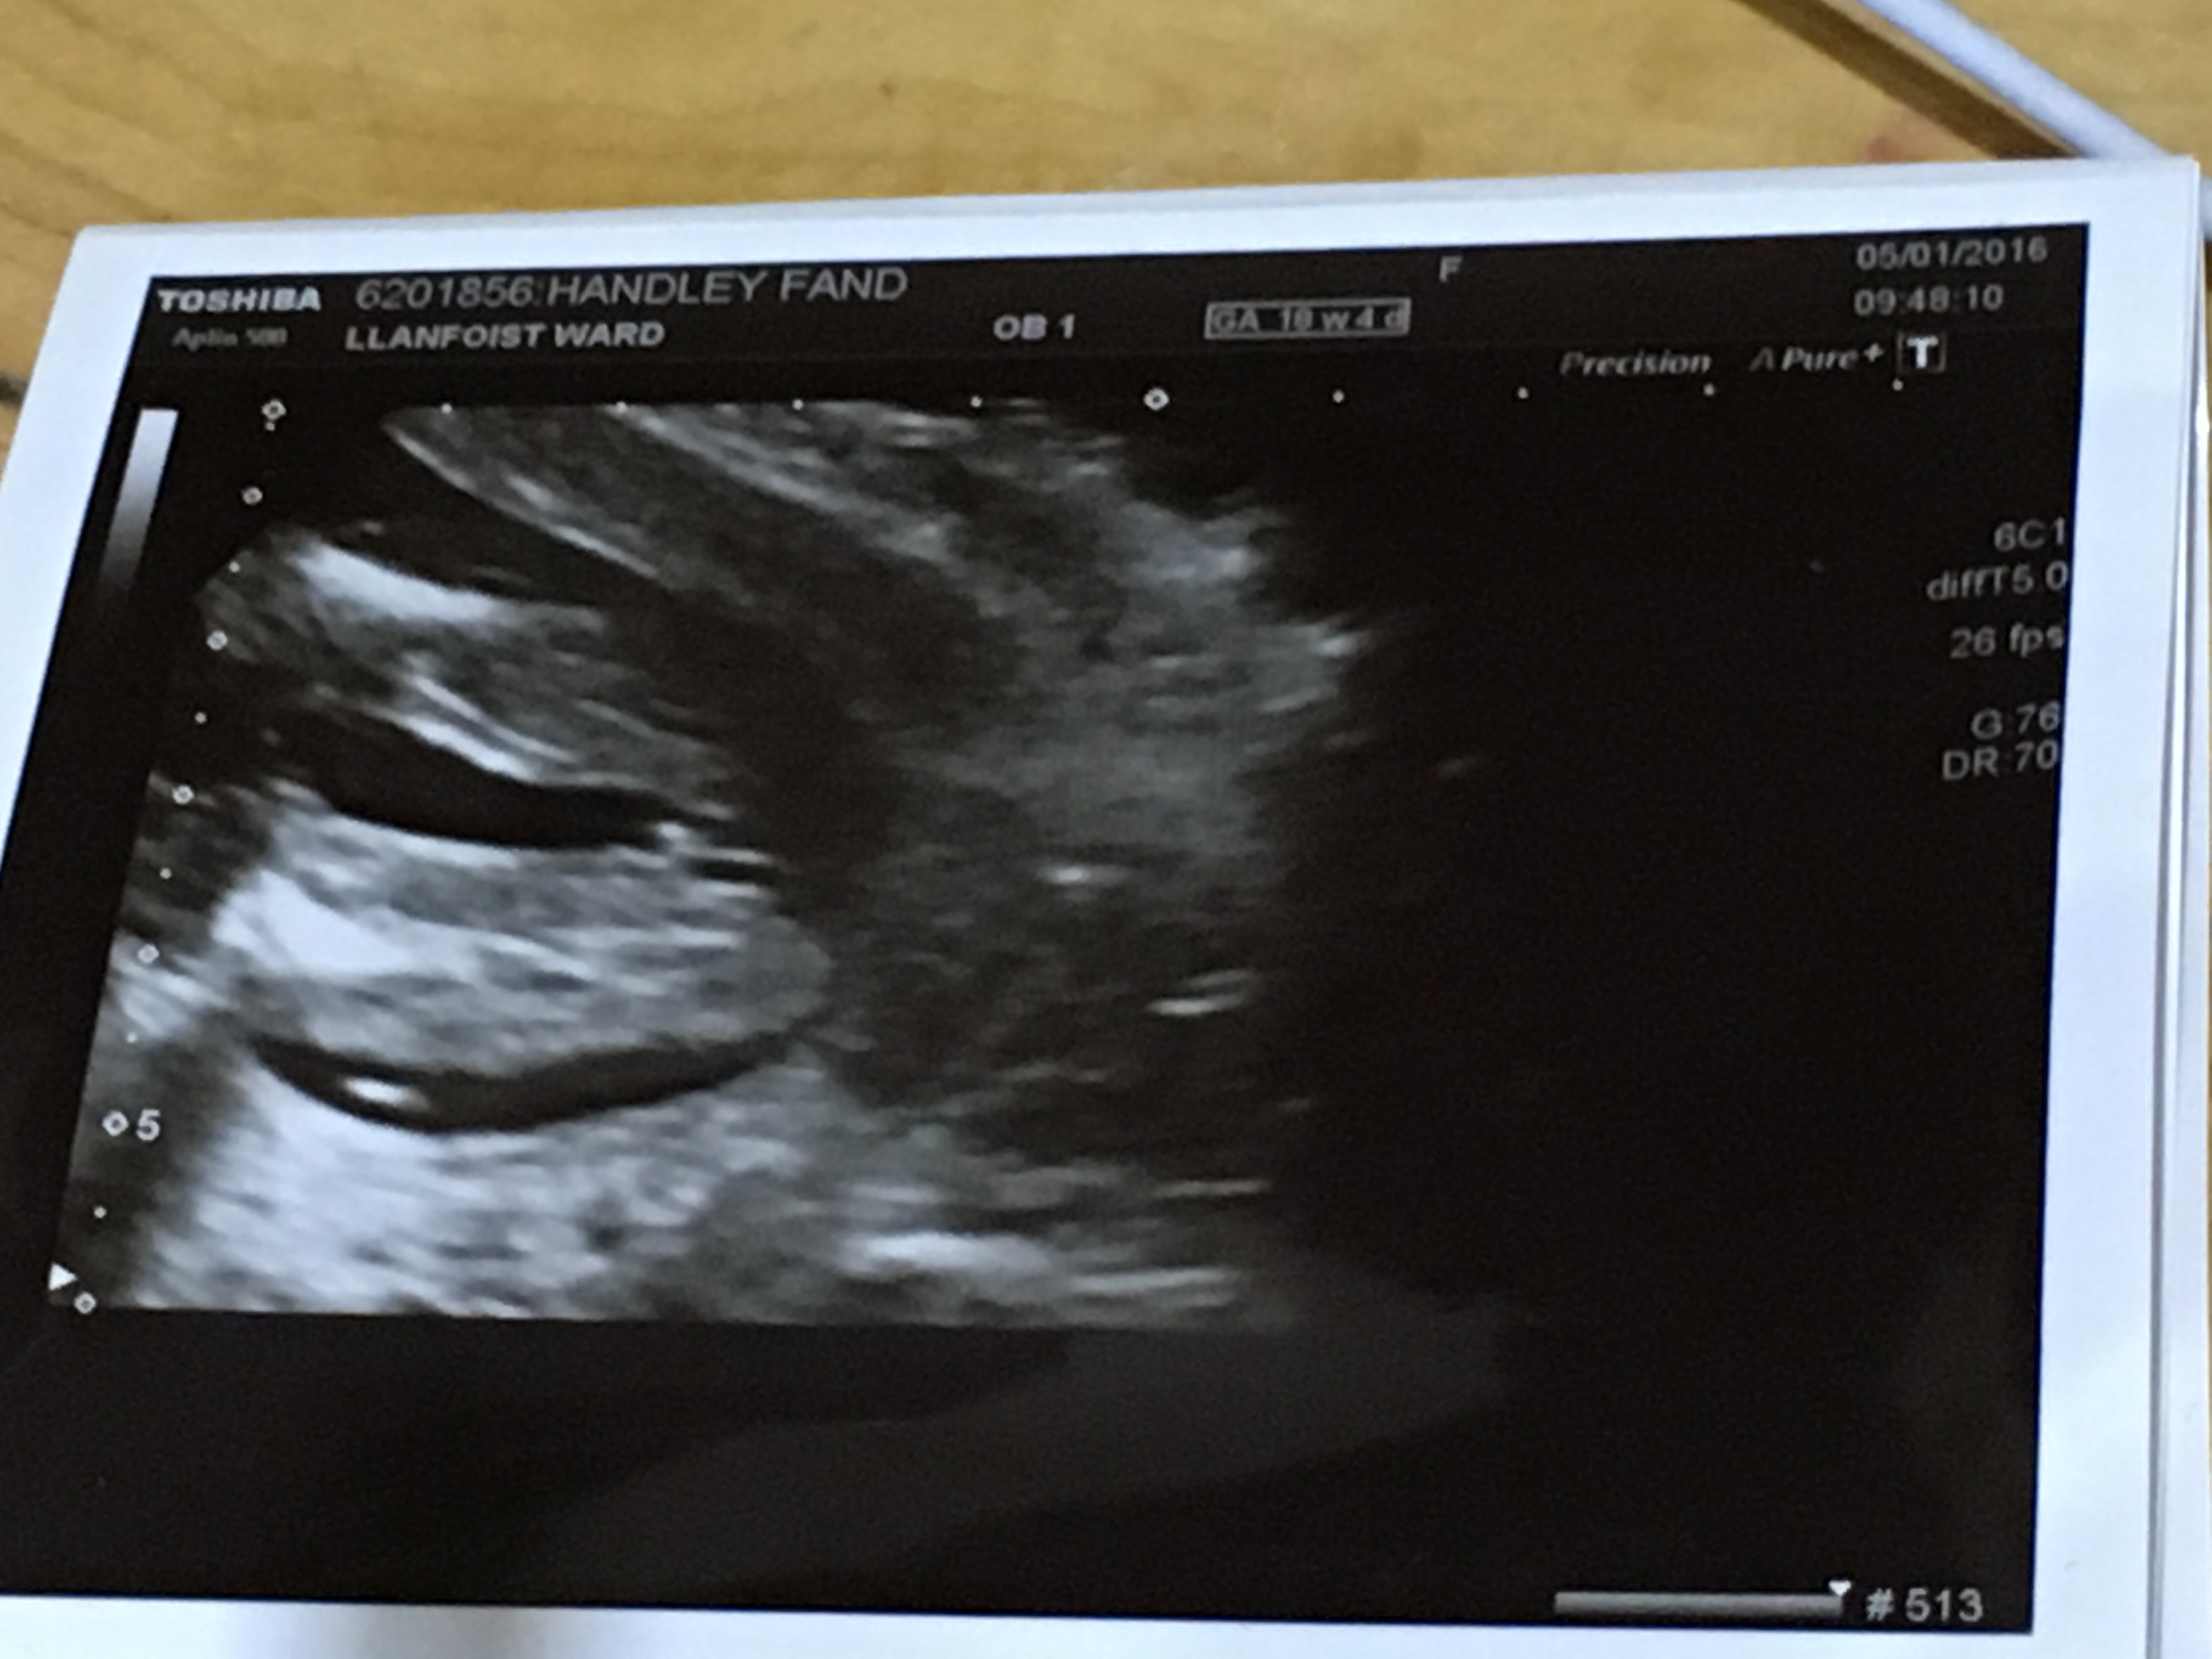

Had an ultrasound at 18+4 . Sonographer told me what she thought but I'd like your opinions for reassurance before I shop X I'll reveal what she told me after as don't want to sway your opinions xxx Thankyou

YEY Thankyou ladies xx sonographer said girl and had another scan today - she said the same xx really wanted reassurance X it was driving me crazy xxx